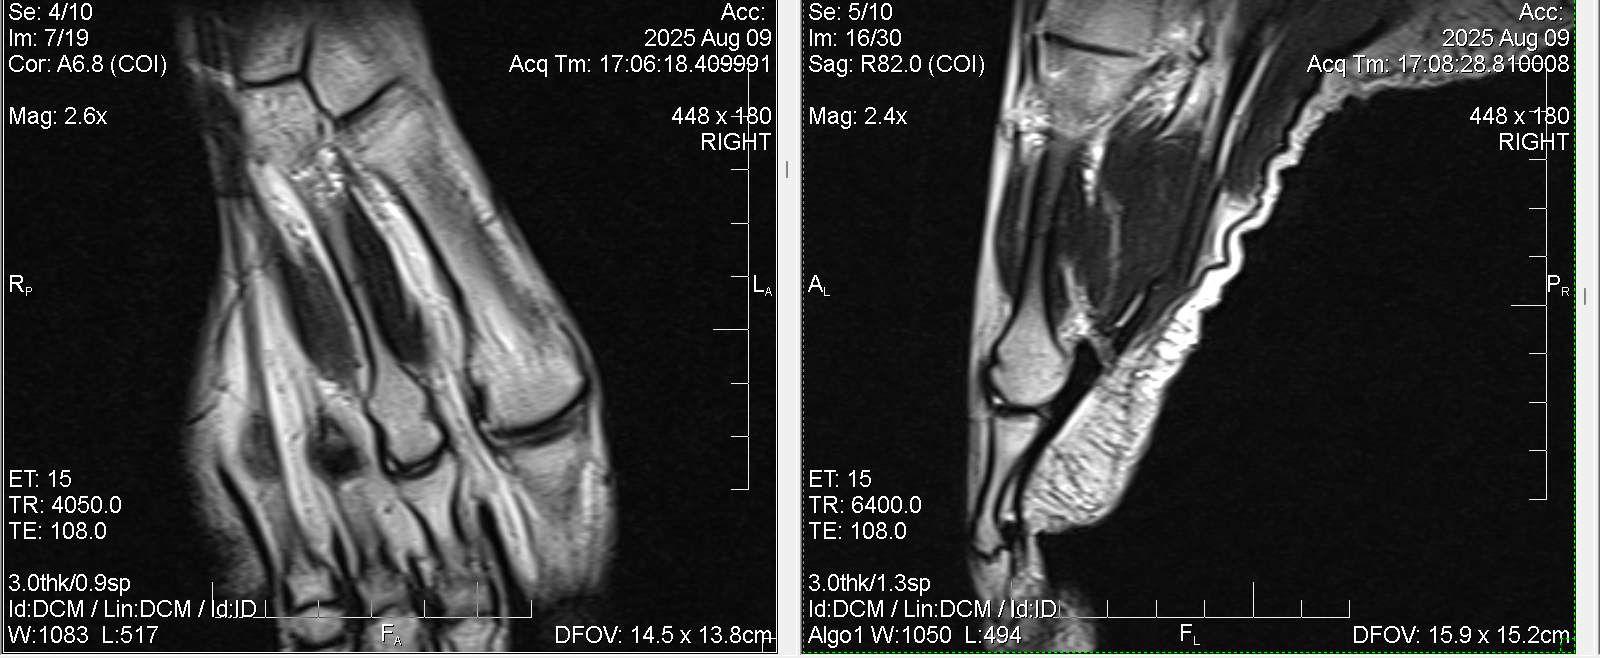

Нужна помощь рентгенологов. Есть ли на этом снимке перелом второй плюсневой кости ( маршевый или стресс)? МРТ Т2

Т1 sag

Примерно в этом месте сверху на коже покраснение.